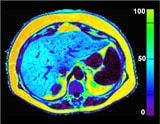

Liver fat fraction map using mDIXON-Quant.

Courtesy: University of Nebraska. Omaha. NE